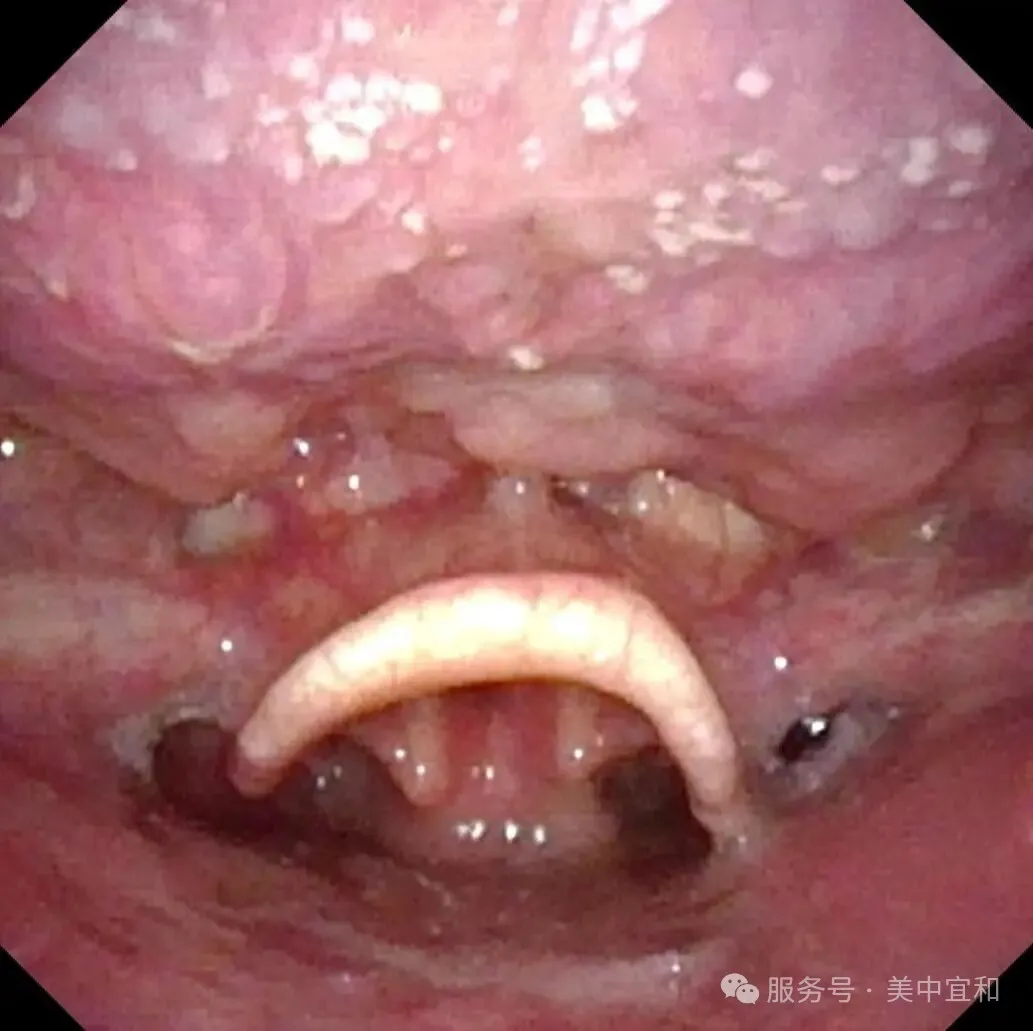

正常會厭部(bu)

會厭左側緣乳頭狀瘤